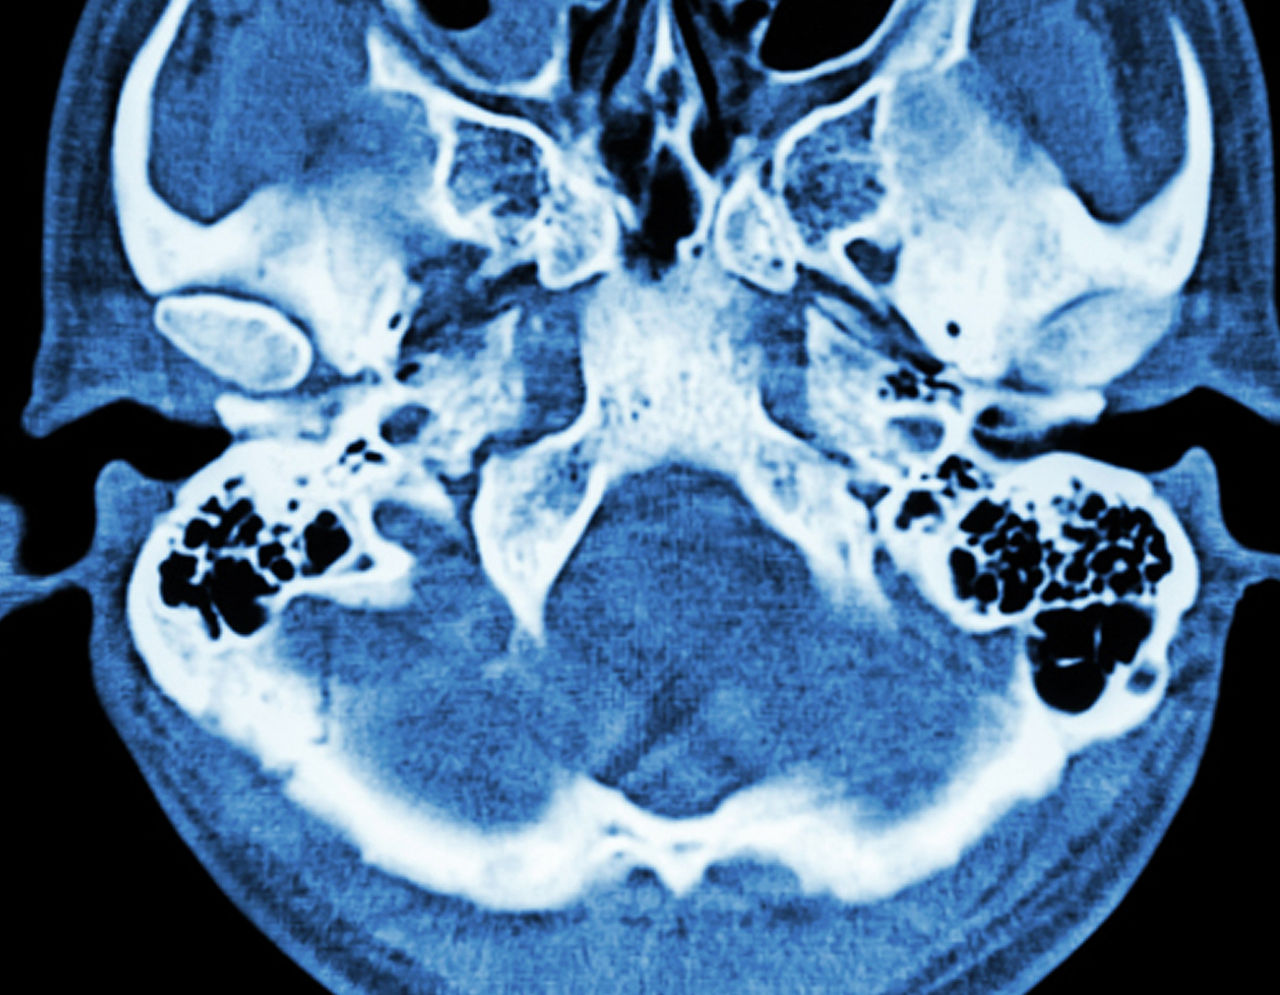

CT scan of brain and base of skull